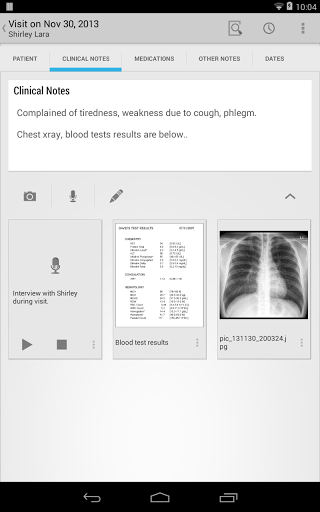

• Pendant les visites des patients, ajouter des notes de visite / médicales comme du texte, une image, un enregistrement vocal ou une écriture manuscrite

• Utiliser la dictée pour écrire automatiquement du texte sur des notes médicales